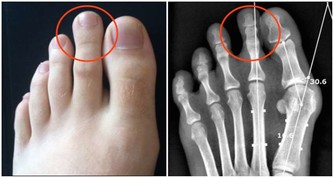

這一種人,千萬別側睡!!!你會後悔終生的…看了就明白了!!

頸椎病患者更適合仰臥,這樣可以順應頸椎的生理彎曲,為達到枕頭支撐頸部的目的,患者最好將蕎麥皮枕頭的形狀稍加整理,使其形成一個中間凹、兩邊凸的形狀,高起的部分相當於自己的拳頭。睡眠時儘量枕著中間凹的部位,開始時不太習慣,經過長期適應,可以最大程度減少睡眠過程中的翻身動作。 蕎麥皮枕頭的適應性強,填充枕頭時,不要填得太滿,否則影響其塑形,填充約70%即可。(蘇玉梅)